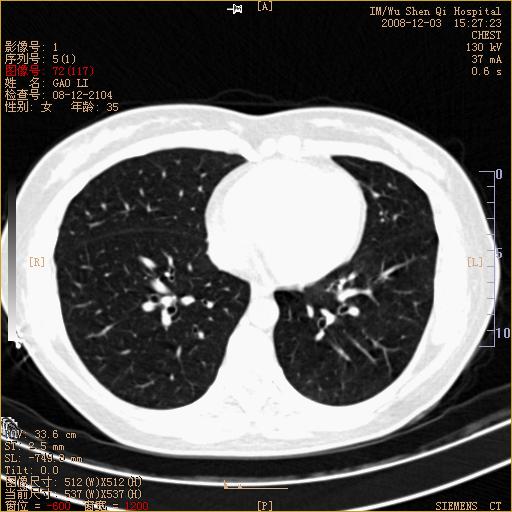

标题: CT16895:女,35岁,反复咳嗽数月,只传部分图像,是否考虑 [打印本页]

标题: CT16895:女,35岁,反复咳嗽数月,只传部分图像,是否考虑

左下肺支扩

典型“印戒征”。

印戒征,支持支扩.

左下肺扩支

印戒征,支扩